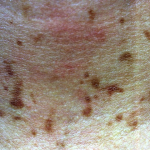

Acute phototoxicity usually occurs within hours of exposure to the phototoxic agent and UV radiation. Symptoms are drug-dose and UV-dose dependent, but at sufficient doses, the patient complains of a burning and stinging sensation on exposed areas, such as forehead, nose, V area of the neck, and dorsa of the hands. Erythema and edema may appear within hours of exposure; in severe cases, vesicles and bullae may develop. Protected areas, such as nasolabial folds, postauricular and submental areas, and areas covered by clothing, are spared . A notable exception to these kinetics is psoralen-induced phototoxicity, in which often the acute response first appears after 24 hours, and peaks at 48 to 72 hours, which is the rationale for administering psoralen plus UVA (PUVA) photochemotherapy doses 48 to 72 hours apart. The phototoxic response usually resolves with a varying degree of hyperpigmentation, which may last for months. At lower drug/UV doses, gradual tanning only, without preceding sunburn-like reaction, can be seen.

Blue-gray pigmentation on sun-exposed areas has been associated with exposure to several agents. One percent to 10 percent of patients taking amiodarone develop this side effect . Chlorpromazine can induce a similar change. The tricyclic antidepressants imipramine and, less commonly, desipramine have also been reported to cause slate-gray pigmentation. A drug metabolite-melanin complex has been postulated to be the cause of this alteration. Chronic exposure to diltiazem, a benzothiazepine calcium channel blocker, has resulted in photodistributed, reticulated, slate-gray pigmentation . Pigmentary incontinence and melanosome complexes are the prominent histologic and electron microscopic findings. Slate-gray pigmentation seen in argyria involves the nail lunulae, mucous membranes, and sclerae. A photochemical reaction in which silver granules are deposited in the dermis results in these pigmentary alterations.

Acute phototoxicity is characterized by individual necrotic keratinocytes and, in severe cases, epidermal necrosis . There may be epidermal spongiosis, dermal edema, and a mild infiltrate consisting of neutrophils, lymphocytes, and macrophages. Slate-gray pigmentation is associated with increased dermal melanin and dermal deposits of the drug or its metabolite. Histologic features of lichenoid eruptions are similar to those of idiopathic lichen planus; however, there may be a greater degree of spongiosis and dermal eosinophilic and plasma cell infiltrates, and a larger number of necrotic keratinocytes and cytoid bodies. In pseudoporphyria, as in porphyria cutanea tarda, there is dermal-epidermal separation at the lamina lucida and deposits of immunoglobulins at the dermal-epidermal junction and surrounding blood vessel walls.